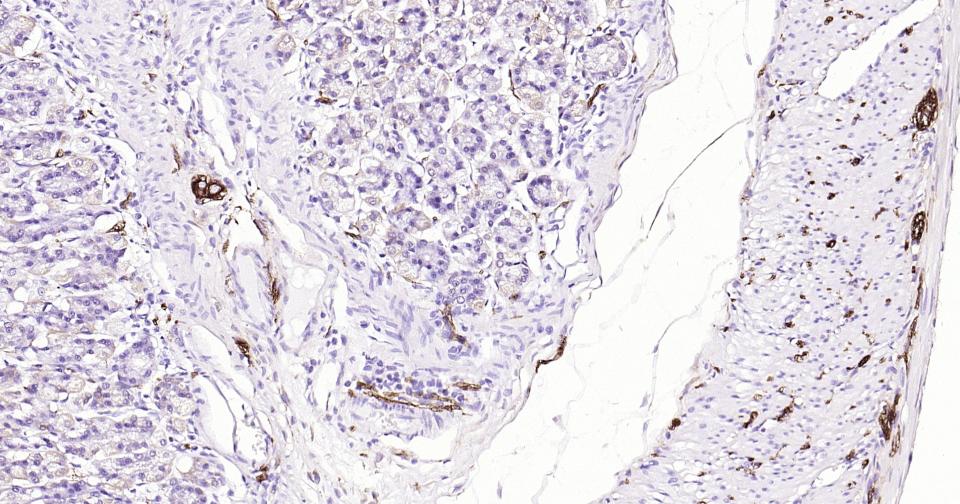

Paraformaldehyde-fixed, paraffin embedded Human Thyroid Tumor; Antigen retrieval by boiling in sodium citrate buffer (pH6.0) for 15 min; Antibody incubation with Tubulin beta-III Monoclonal Antibody, Unconjugated(bsm-52323R) at 1:200 overnight at 4°C, followed by conjugation to the SP Kit (Rabbit, SP-0023)and DAB (C-0010) staining.